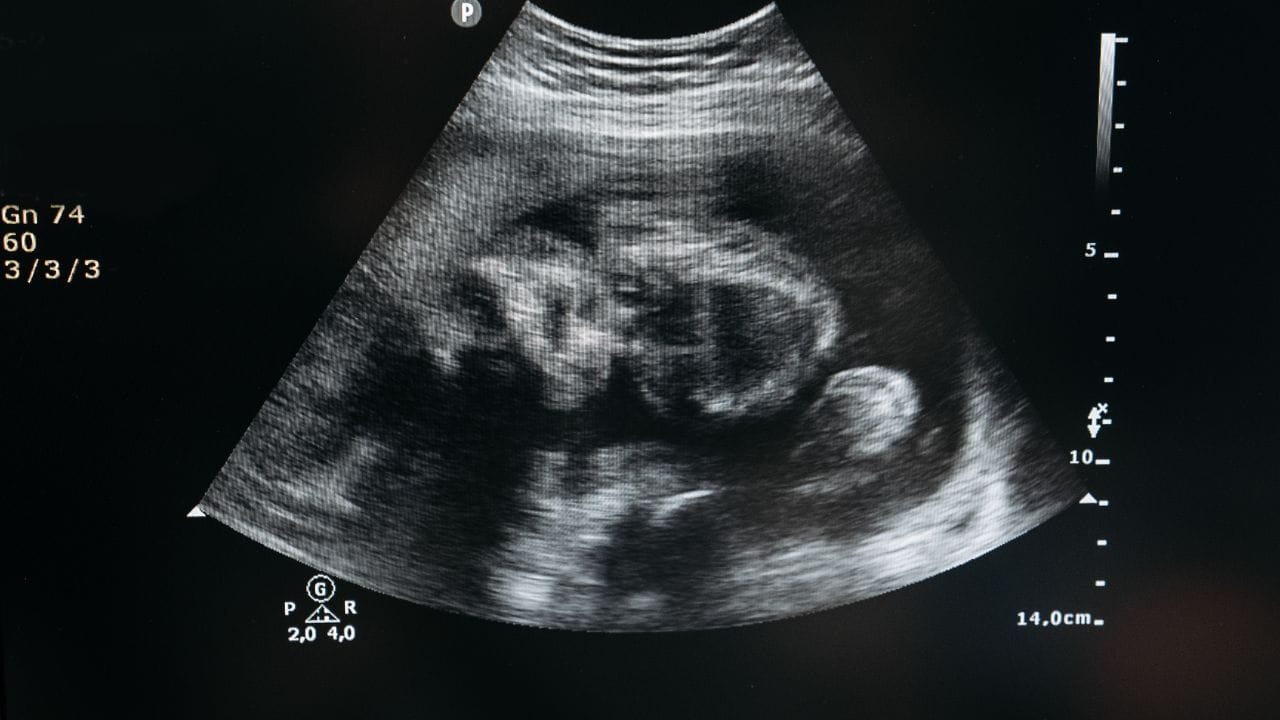

મહિલાઓના શરીરમાં અનેક શારીરિક ફેરફાર થતાં હોય છે. પ્રેગ્નન્સીમાં મહિલાઓને અનેક પ્રકારની સમસ્યાઓનું પણ જોખમ હોય છે. આ સમસ્યાઓમાં એક્ટોપિક પ્રેગ્નન્સીને પણ સામેલ કરવામાં આવે છે. આ પ્રેગ્નન્સી સાથે જોડાયેલી એક ગંભીર સમસ્યા છે. આ સ્થિતિમાં બાળક ગર્ભાશયની બહાર વિકાસ થાય છે.આ એક ઈમરજન્સી સ્થિતિ છે. જેમાં સમયસર સારવાર ન મળતા મહિલાના જીવને પણ જોખમ રહે છે.

આ સ્થિતિમાં મહિલાને તીવ્ર દુખાવો તેમજ હેવી બ્લીડિંગ થાય છે. તો આપણે ગાયનેકોલોજિસ્ટ પાસેથી જાણીએ એક્ટોપિક પ્રેગ્નન્સી થવાનું કારણ શું છે.એક્ટોપિક પ્રેગ્નન્સી શું હોય છે. સામાન્ય રીતે પ્રેગ્નન્સીમાં એગ્સ ફર્ટીલાઈઝ થાય છે. ત્યારે તે ફૈલોપિયન ટ્યુબથી થઈ ગર્ભાશય તરફ જાય છે. ત્યારબાદ ફર્ટિલાઈઝ એગ લાઈનિંગમાં ઈપ્લાન્ટ થઈ ભ્રૂણ બને છે. પરંતુ એક્ટોપિક પ્રેગ્નન્સીમાં આ ફર્ટિલાઈઝ એગ ગર્ભાશયને બદલે અન્ય જગ્યા પર ઈમ્પલાન્ટ થાય છે.

મોટાભાગના કેસમાં ફૈલોપિયન ટ્યુબમાં આ ઈમ્પલાટેશન શરુ થાય છે. આ સ્થિતિને ટ્યુબલ પ્રેગ્નન્સી પણ કહેવામાં આવે છે. જ્યારે કેટલાક કેસેમાં ભ્રૂણ ગર્ભાશયની બહાર અન્ય અંગો જેમ કે, ઓવરી, ગર્ભાશય કે અન્ય જગ્યાએ વિકસિત થઈ શકે છે.